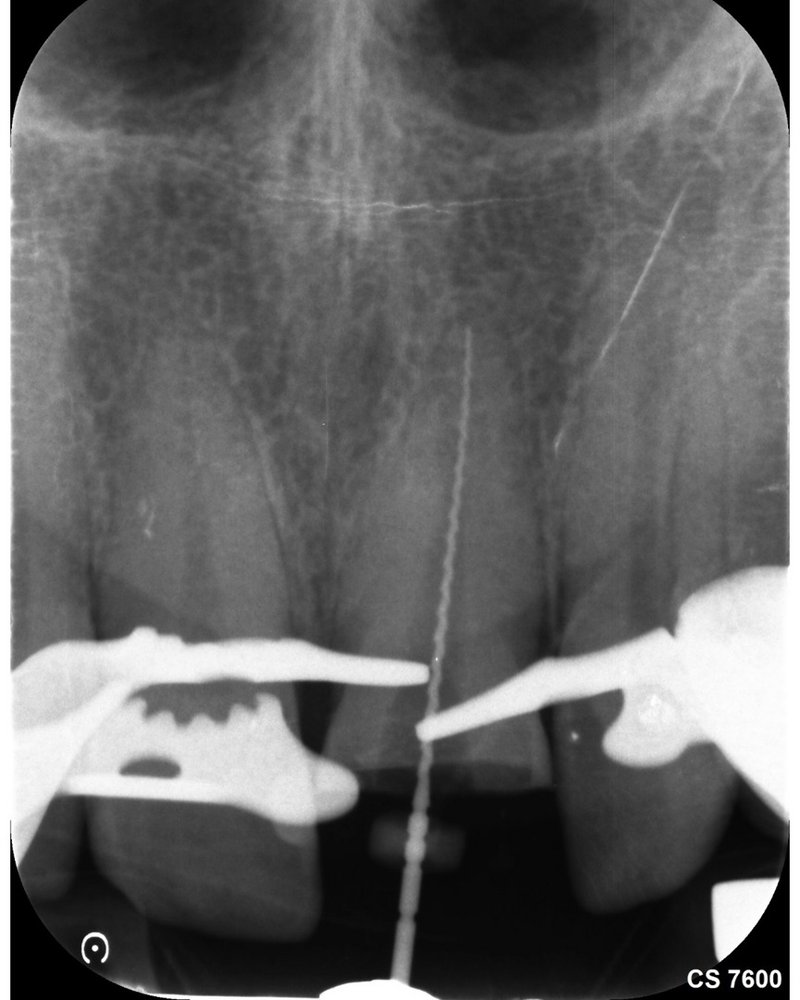

Zugehöriges Röntgenbild vor der Wurzelkanalbehandlung

Kontrastaufnahme zur Längenbestimmung des Wurzelkanals